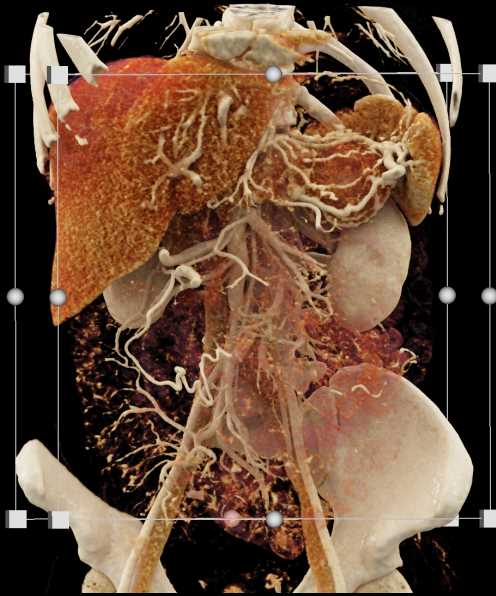

Neuroendocrine Tumor Pancreas